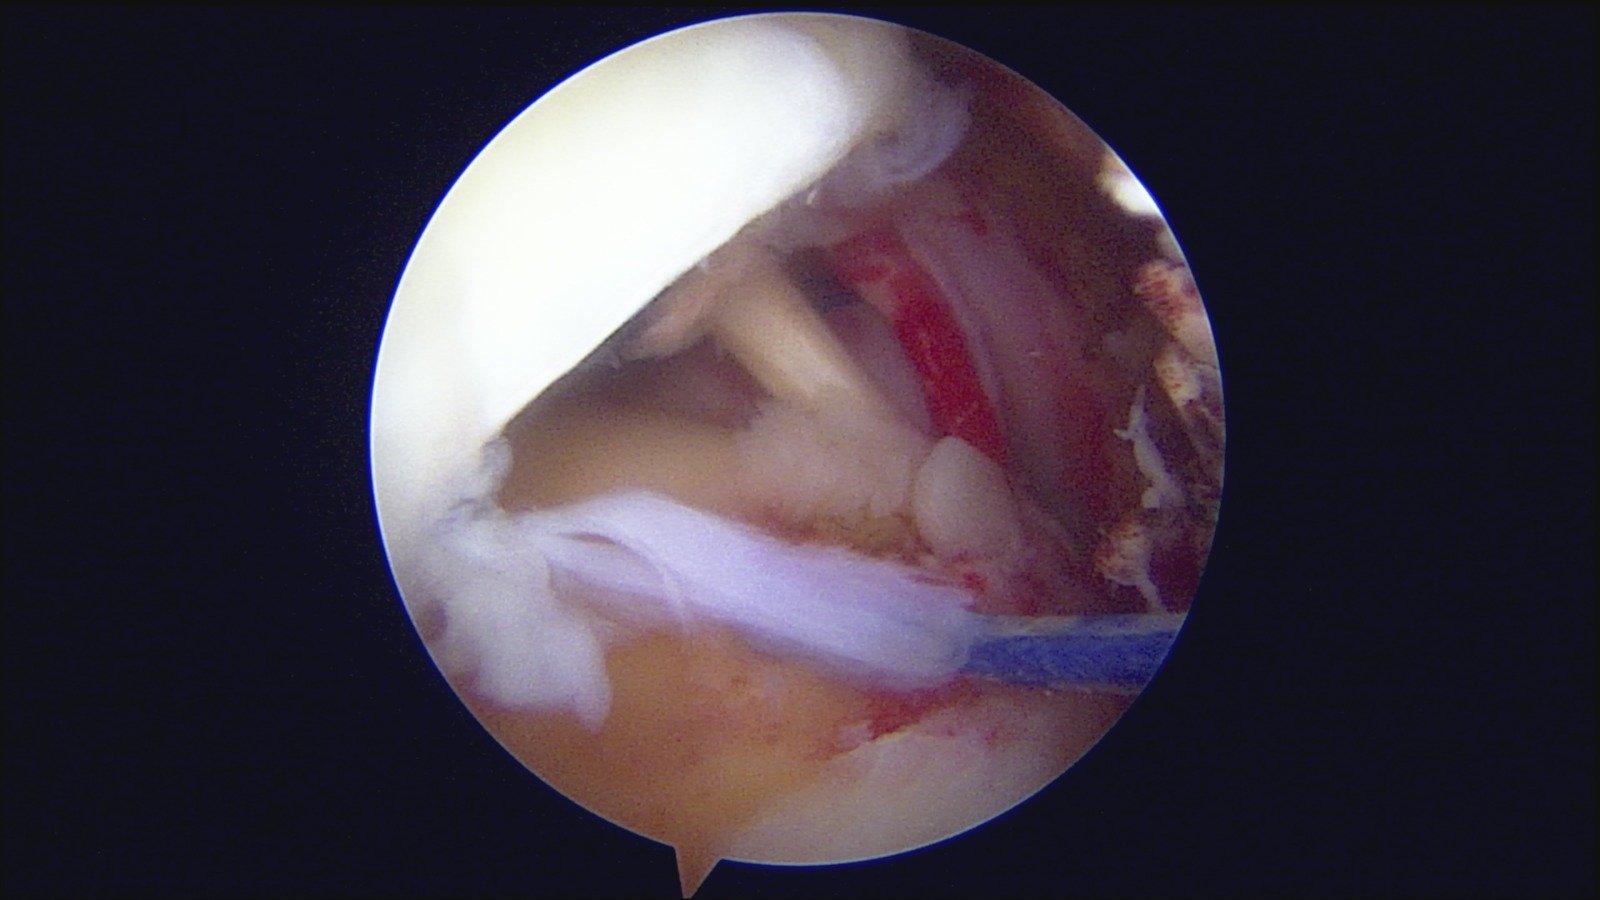

GalleryShoulder rotator cuff repair Meniscus root repair Meniscus repair Bankart repair for recurrent shoulder dislocation ACL reconstruction Machines Instruments